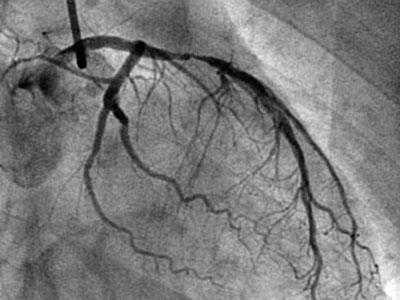

揭秘手术台丨冠脉造影原来是这么做的!

冠状动脉造影术

【医学科普】带你一起进入冠脉造影和心脏支架植入现场

做冠脉造影后人活不久了吗?带来的这4个风险,要了解清楚

冠状动脉造影

(冠状动脉造影检查)

心脏造影检查血管堵塞多少做支架

【专病专讲】冠心病之冠脉造影检查

心脏造影_什么情况需要做心脏造影

心脏造影有风险不能随便做?出现这几种情况,该检查一下心脏

得了冠心病,到底做心脏造影还是cta,了解这些

冠脉造影医保报销比例冠县社保局【心科普】为什么要做冠脉造影检查